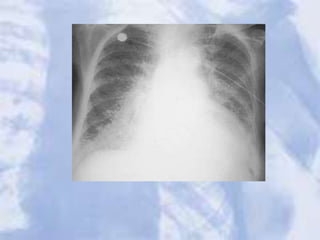

CHF:a great deal of accentuated interstitial markings,

Curly lines, and an enlarged heart. Normally indistinct

upper lobe vessels are prominent but are also masked

by interstitial edema.

24 hours after diuretic therapy